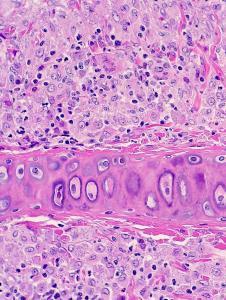

Leishmaniasis en hurón

Ésta es la primera descripción de leishmaniasis en un hurón, eficaz y diligentemente trabajada, como siempre, por Jacobo Giner de Centro Veterinario Menescalia, con la colaboración de la Universidad de Zaragoza y publicada en Veterinary Parasitology: Regional Studies and Reports 19:100369, 2020. doi: 10.1016/j.vprsr.2020.100369. Con esta publicación, Jacobo logró el 2º premio de los Premios de Divulgación Científica 2020 del Ilustre Colegio de Veterinarios de Valencia; aunque Jacobo está acostumbrado a ganar premios y seguro que tiene entre ceja y ceja el primer premio, nuestras más sinceras felicitaciones por este extraordinario logro y ánimos para que siga persiguiendo el primer premio y así pueda invitarme a esas cenas que me debe en el restaurante de cocina de autor Almoraduz, Puerto Escondido (Oaxaca). No se pierdan el taller de Medicina y Patología de Hurones del Congreso Solidario de Medicina y Conservación de Fauna Exótica y Salvaje de Puerto Escondido con Jacobo, Mike Garner y un servidor, va a ser extraordinariamente rico en medicina, patología y humor...cuando de una vez por todas podamos celebrar este congreso. ¡Bravo, Jacobo!.